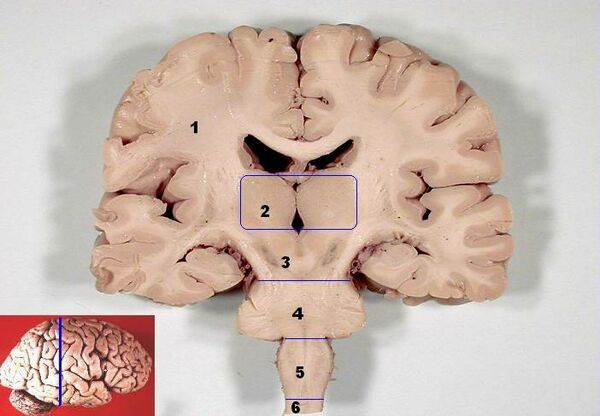

Тала́мус, иногда — зри́тельные бугры (лат. thalamus; от др.-греч. θάλαμος «комната, камера, отсек») — отдел головного мозга, представляющий собой большую массу серого вещества, расположенную в верхней части таламической области промежуточного мозга хордовых животных, в том числе и человека. Впервые описан древнеримским врачом и анатомом Галеном. Таламус — это парная структура, состоящая из двух половинок, симметричных относительно межполушарной плоскости. Таламус находится глубже структур большого мозга, в частности коры или плаща. Под таламусом расположены структуры среднего мозга. Срединная (медиальная) поверхность обеих половинок таламуса одновременно является верхней боковой стенкой третьего желудочка головного мозга[1][2][3].

Таламус расположен вблизи центра мозга и входит в число структур таламической области промежуточного мозга. Он залегает под структурами большого мозга, но возвышается над структурами среднего мозга. Восходящие аксоны, исходящие из нейронов ядер таламуса, формируют пучки миелинизированных нервных волокон. Эти пучки нервных волокон обильно проецируются на различные области коры больших полушарий головного мозга во всех направлениях. Медиальная поверхность обеих половинок таламуса одновременно является верхней частью боковой стенки третьего желудочка головного мозга. Она соединена с соответствующей медиальной поверхностью противоположной половинки таламуса плоской полосой белого вещества. Эта полоса представляет собой пучок миелинизированных нервных волокон и называется межталамическим сращением, или промежуточной массой третьего желудочка, или срединной комиссурой (срединной спайкой) таламуса.

Таламус состоит из нескольких отдельных областей серого вещества. Эти области представляют собой группы таламических ядер, разделённых областями белого вещества. Белое вещество, разделяющее и облегающее отдельные таламические ядра и группы ядер, представляет собой пучки миелинизированных нервных волокон. Кроме того, в таламусе выделяют также особые группы нейронов, отличающихся по своему гистологическому строению и биохимическому составу от остальной части таламуса, такие, как перивентрикулярное ядро, внутрипластинчатые ядра, так называемое ограниченное ядро и другие[3]. Эти отличающиеся по своей гистологической структуре и биохимическому составу от остальных ядер таламуса особенные ядра обычно группируют в так называемый аллоталамус, в противоположность «типичным» таламическим ядрам, которые группируют в так называемый изоталамус[7].

Ядра таламуса на основании особенностей их анатомо-гистологической структуры и цитоархитектоники можно подразделить на шесть групп: передние, медиальные, боковые, ретикулярные, внутрипластинчатые ядра и ядра средней линии. Тонкий Y-образный слой миелинизированных нервных волокон, так называемая внутренняя мозговая пластинка, разграничивает между собой переднюю, срединную и боковую группы таламических ядер. У человека передняя и срединная группы таламических ядер содержат всего по одному большому ядру, называемому соответственно передним дорсальным и медиальным дорсальным ядрами таламуса. Между тем боковая группа ядер таламуса человека подразделяется на дорсальный и вентральный уровни. Дорсальный уровень боковых ядер таламуса человека состоит из бокового дорсального, бокового заднего ядер и ядер подушки таламуса. Вентральный уровень боковых ядер таламуса человека, в свою очередь, состоит из вентрального переднего, вентрального бокового, вентрального задне-бокового и вентральных задних медиальных ядер[8].